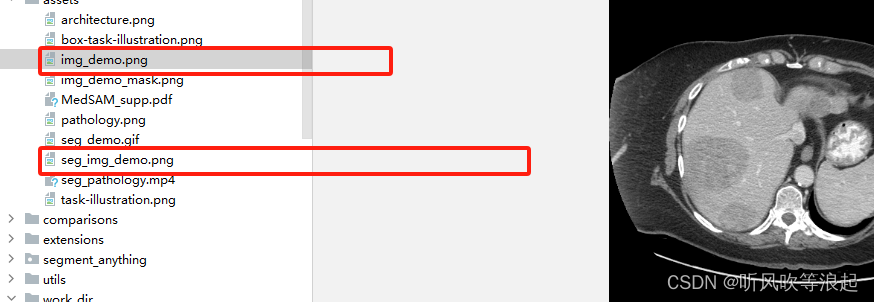

这里会自动推理assets下的demo图像,然后保存在这里

不过这里推理后的图像是黑的,可以根据下面代码显示:

import matplotlib.pyplot as plt

img_path = 'assets/seg_img_demo.png'

img =plt.imread(img_path)

plt.imshow(img)

plt.show()